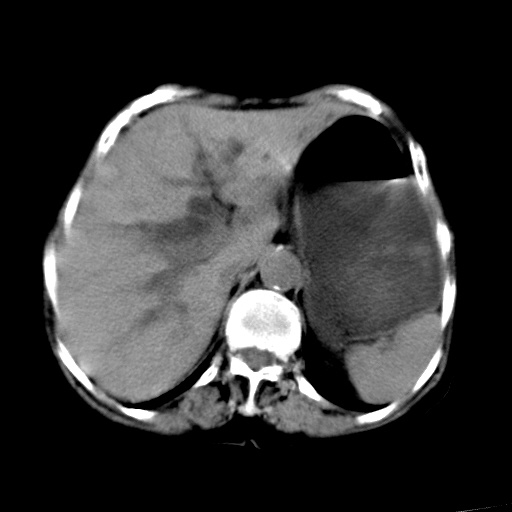

以下是引用杀毒软件在2009-3-4 17:38:00的发言:[br]为何没有喝照影剂呀? 胆总管及肝内胆管扩张,增强吧。[br][br]考虑-----十二指肠占位----建议----十二指肠镜检查[br][br]

以下是引用jiangjing在2009-3-4 17:45:00的发言:[br]低位胆道梗阻。十二指肠降段局部管壁增厚。扫描效果不理想,建议ct增强及ercp。

以下是引用杀毒软件在2009-3-4 17:38:00的发言:[br]为何没有喝照影剂呀? 胆总管及肝内胆管扩张,。增强吧。[br][br]考虑-----十二指肠占位----建议----十二指肠镜检查[br][br][br][br][本贴已被 杀毒软件 于 2009-3-4 17:56:38 修改过]